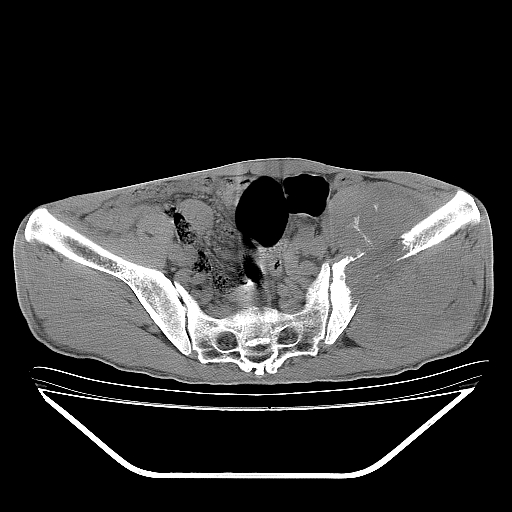

以下是引用天南地北在2007-10-4 18:01:00的发言:[br][br]考虑左髂部恶性肿瘤(溶骨性骨质破坏+软组织肿块影+残留骨质);以滑膜肉瘤可能性大。[br]建议穿刺活检

以下是引用liuyue在2007-10-4 23:38:00的发言:[br]左髂部恶性肿瘤,建议穿刺活检,或先做肺部检查,除外肺癌转移之可能。